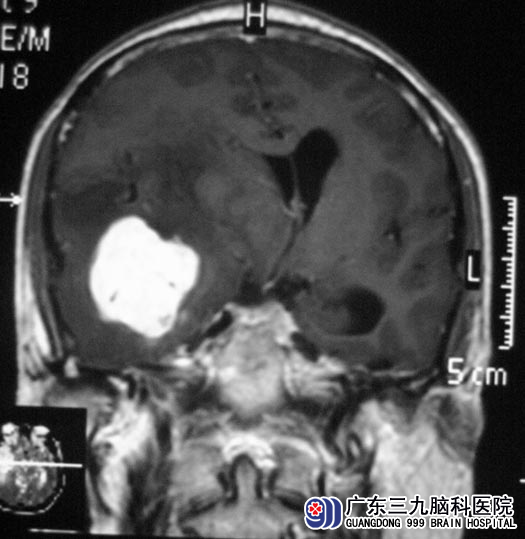

在广东三九脑科医院进一步检查发现:1、右侧颞部占位病灶,考虑血管外皮细胞瘤可能性大,待排间变性脑膜瘤或脑外巨大海绵状血管瘤;2、幕上脑室系统扩大,右侧大脑镰下疝,3、脑白质散在脱髓鞘灶。

5月22日,由综合神经外科 鲁明主任主刀,在全麻下行右侧颞叶占位病变切除术,术中显微镜下见肿瘤紧贴颅底硬脑膜生长,肿瘤表面有大量小血管缠绕,予镜下分块切除,经过顺利。术后康复满意。病理结果为:脑膜瘤(透明细胞型,WHO II级)。